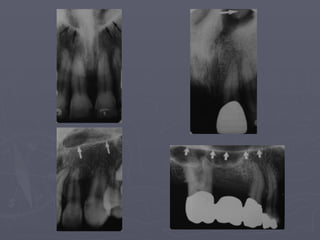

Nutrient canals :

The arrows above

identify nutrient

Canals.

They are most often seen

in

Persons with thin bone

and in

Those with high blood

pressure

Or advanced

periodontitis.

Nutrient canals